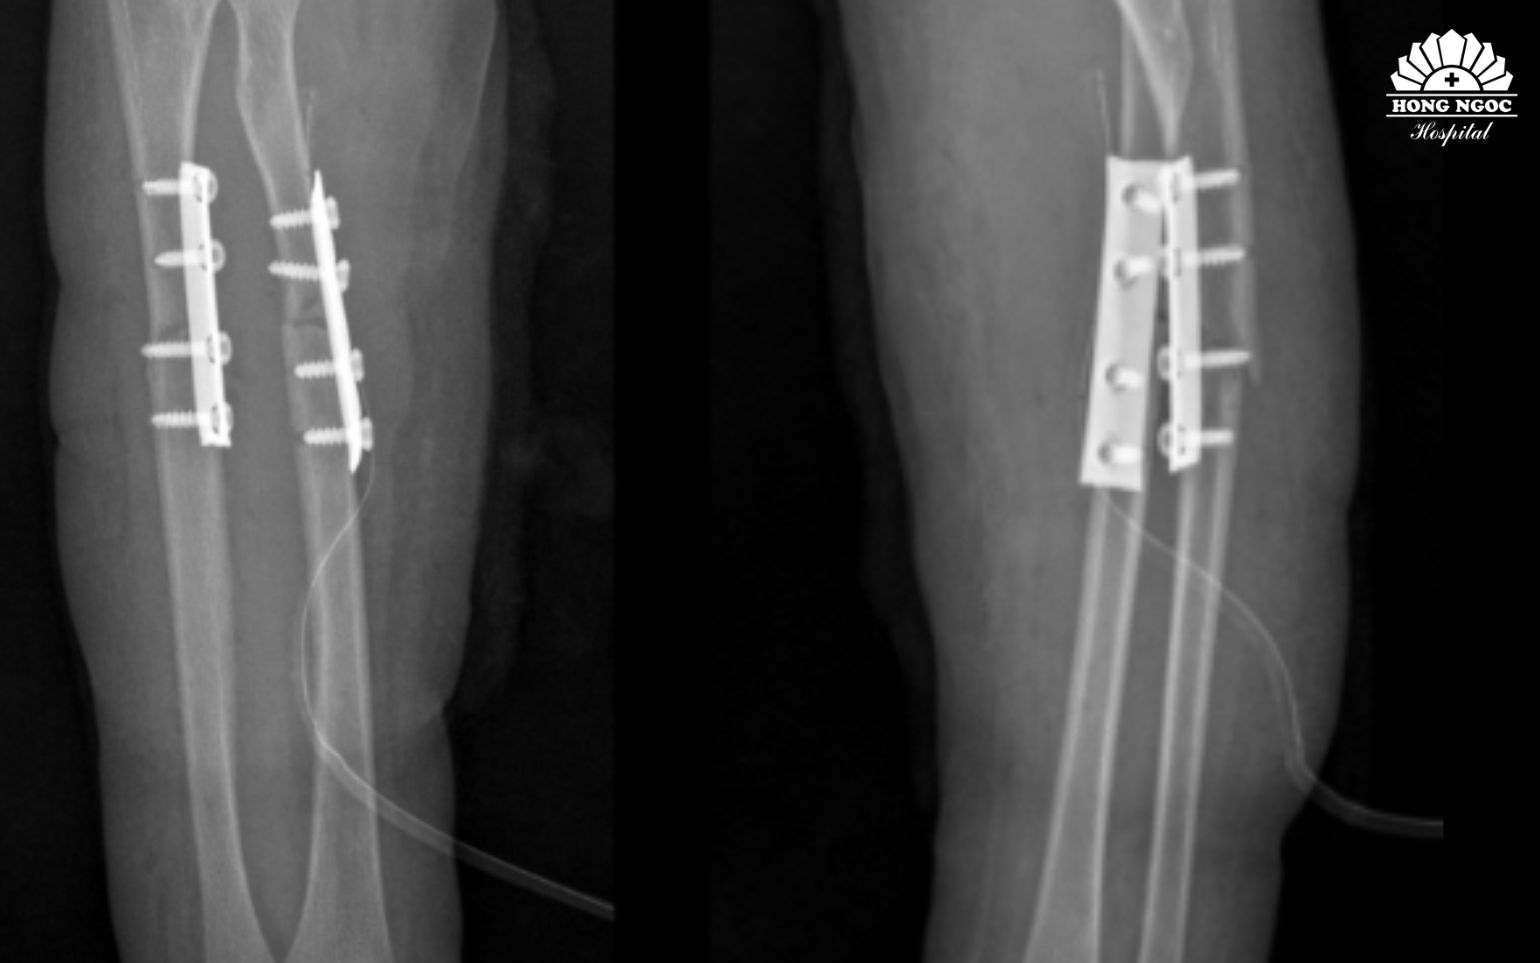

Phẫu thuật kết hợp xương cố định xương gãy, phục hồi vận động sớm

Sau hơn 1 giờ phẫu thuật, dưới sự hỗ trợ của hệ thống máy C-arm, ê-kíp phẫu thuật tiến hành nắn chỉnh trục xương giúp đưa hai đầu xương gãy và mảnh xương di lệch về đúng vị trí giải phẫu, khôi phục chiều dài và chức năng sấp, ngửa của cẳng tay. Sau đó, phẫu thuật viên đặt nẹp vít cố định nhằm giữ vững hai đoạn xương, tạo điều kiện cho quá trình liền xương diễn ra đúng vị trí giải phẫu, tránh nguy cơ sai lệch hoặc biến dạng. Toàn bộ quá trình phẫu thuật được thực hiện qua một đường mổ nhỏ ở phía trước. Chỉ với một đường tiếp cận này, phẫu thuật viên có thể nắn chỉnh và cố định đồng thời cả hai xương gãy, giúp giảm tổn thương phần mềm, hạn chế mất máu và giảm đau sau mổ cho bệnh nhi.